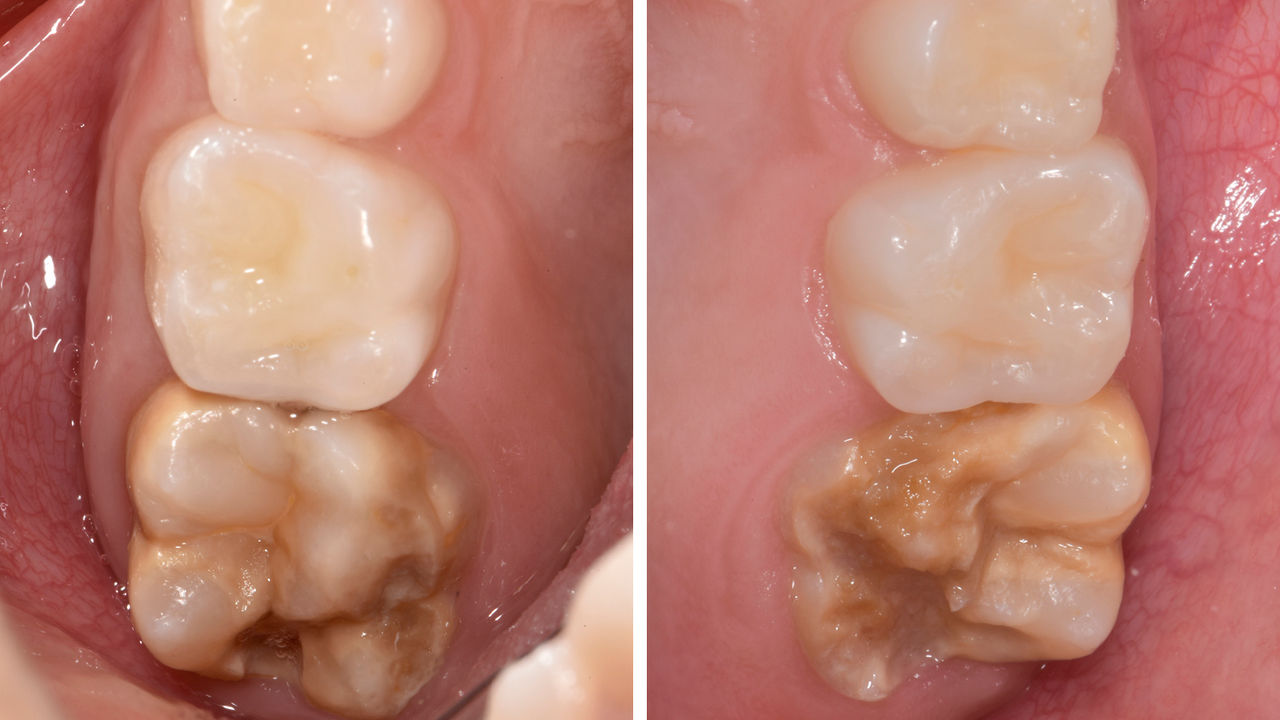

90 dakikada ikinci sağ alt molar

CEREC Tessera onleyi

20 yaşında kadın hasta sağ alttaki 2. molar için endodontik tedavisi aldı. Yeni yüksek dayanımlı seramik CEREC Tessera ALD'den klinikte bir onley üretilmiştir.

Önce: Endodontik tedaviyi izleyen preoperatif klinik senaryo.

Sonra: CEREC Tessera onley bağlandıktan 1 ay sonra.

Dr. Aniruddha Nene

Pune, Hindistan